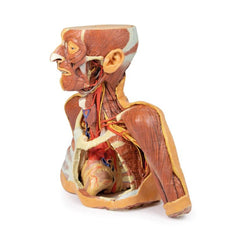

The hilum of a lung is the point at which visceral and parietal pleura meet and functions with the pulmonary

ligament as the lungs only connection with the rest of the body. This connection includes the Pulmonary Artery,

Superior and Inferior Pulmonary Veins, Main Bronchi, Nerves and Lymphatics.

As the definition of an artery

involves carrying blood AWAY from the heart, this will be deoxygenated blood in the pulmonary system, in

contrast with the systemic circulation. Similarly, veins carry blood TOWARDS the heart, meaning it will be

oxygenated in the pulmonary system.